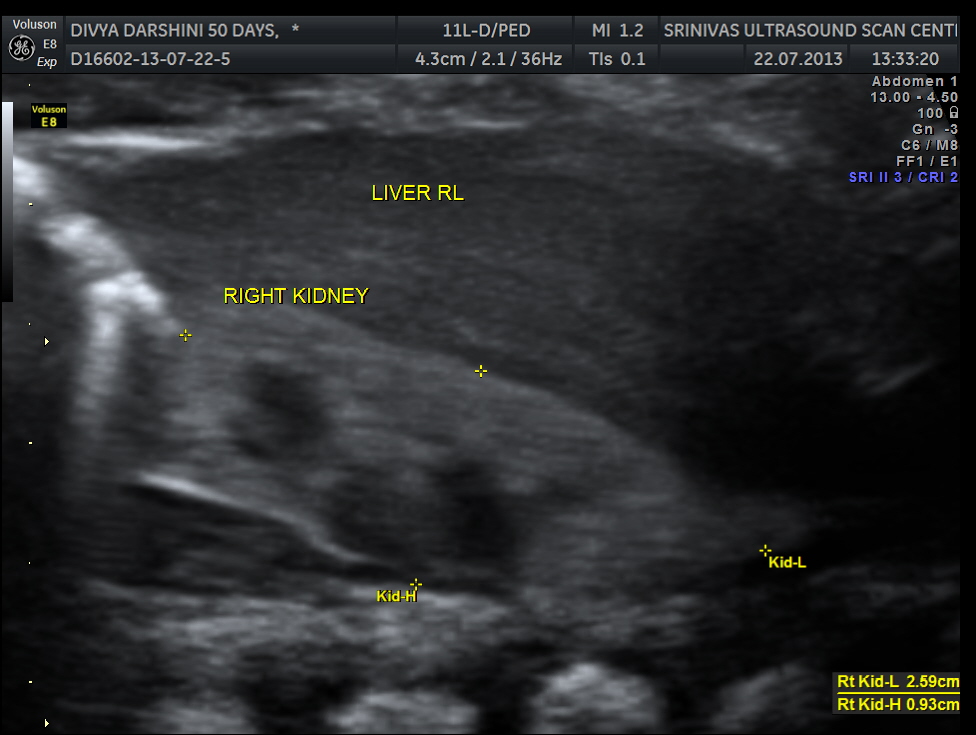

https://kriznanultrasoundimages.com/2013/05/12/tetralogy-of-fallot-tof/ at this time there was a revision of the cardiac findings : LEFT ATRIAL ISOMERISM WITH TETRALOGY OF FALLOT The irregular rhythm was not made out now. Apart from this the foetus has symmetrical IUGR and oligohydramnios Now the child was brought when she was 51 days old . She was born prematurely at 33 weeks of gestation . She had been seen at three higher institutions . The paediatric cardiologist has given a working diagnosis of CONO TRUNCAL VSD. But the catch was that the child had renal dysfunction with s .creatinine around 2 mgms and the ultrasound could not visualise the left kidney. The right kidney was reported to be hyperechoic . The following 2 pictures were of the fetal kidneys , as seen during the scan earlier.

The following two pictures show the hyperechoic kidneys of the child with mild pelvi calyceal dilatation . The kidneys were picked up only with the 11 mhz transducer.